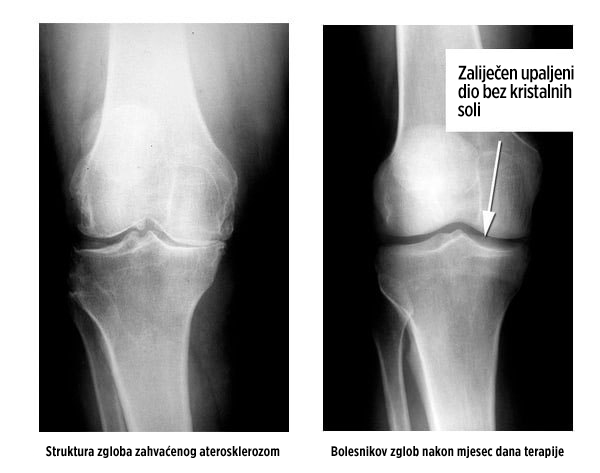

Rekonstrukcija zgloba kolena pogođenog aterosklerozom. Pacijentkinja je tokom mesec dana terapije koristila Nautubone gel.

Struktura zgloba i njegova pokretljivost potpuno su obnovljeni. Bez bola.